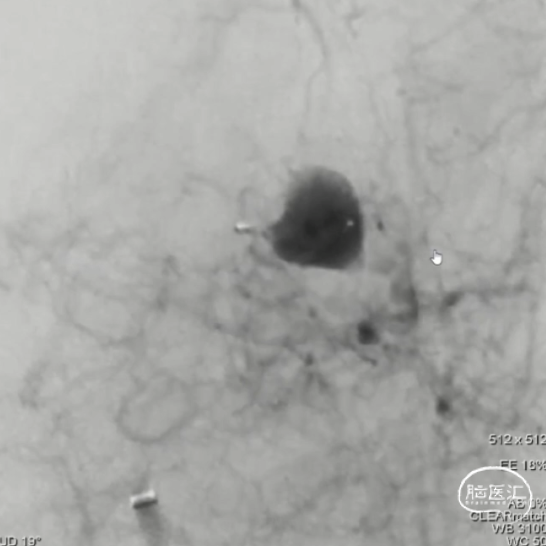

WEB™经由VIA™微导管送入动脉瘤瘤腔并完全释放。术后即刻造影显示WEB™尺寸合适,贴壁良好,分支等血流通畅。解脱后再次造影,可见动脉瘤瘤腔内有明显造影剂滞留。

经造影可见WEB™尺寸合适,贴合瘤壁。解脱后,再次造影可见动脉瘤瘤腔内有明显造影剂滞留。WEB™对分支血流有影响,使用支架保护分支。